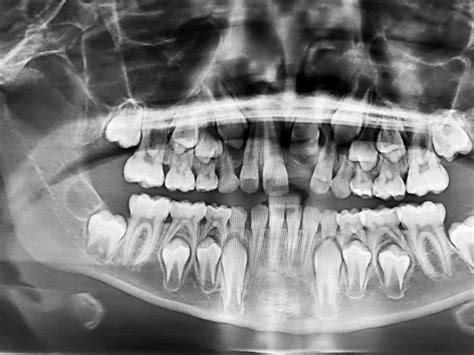

Las radiografías de un niño de 6 años, la primera vez que las ves, dan un poco de miedo, porque puedes ver los dientes de leche y todas las definitivas escondidas debajo. Cada vez que cae un diente de leche lo habitual es que erupcione un diente definitivo ese espacio. Por ello, cuando miramos una radiografía de un niño menor de 13 años podemos ver una tanda de dientes y debajo otra hilera de dientes.

Al caer los dientes de leche lo que observamos son las coronas o parte visible en boca del diente. Sobre los 6 años de edad, el niño experimenta la caída del primer diente anterior y la salida del primer diente definitivo. Generalmente el primer diente en caer y aparecer suele ser el incisivo central inferior.

En las radiografías, podemos identificar problemas como:

- Agenesia (ausencia de dientes definitivos)

- Dientes impactados o transpuestos

- Problemas de espacio en la boca

- Anomalías en la erupción dental